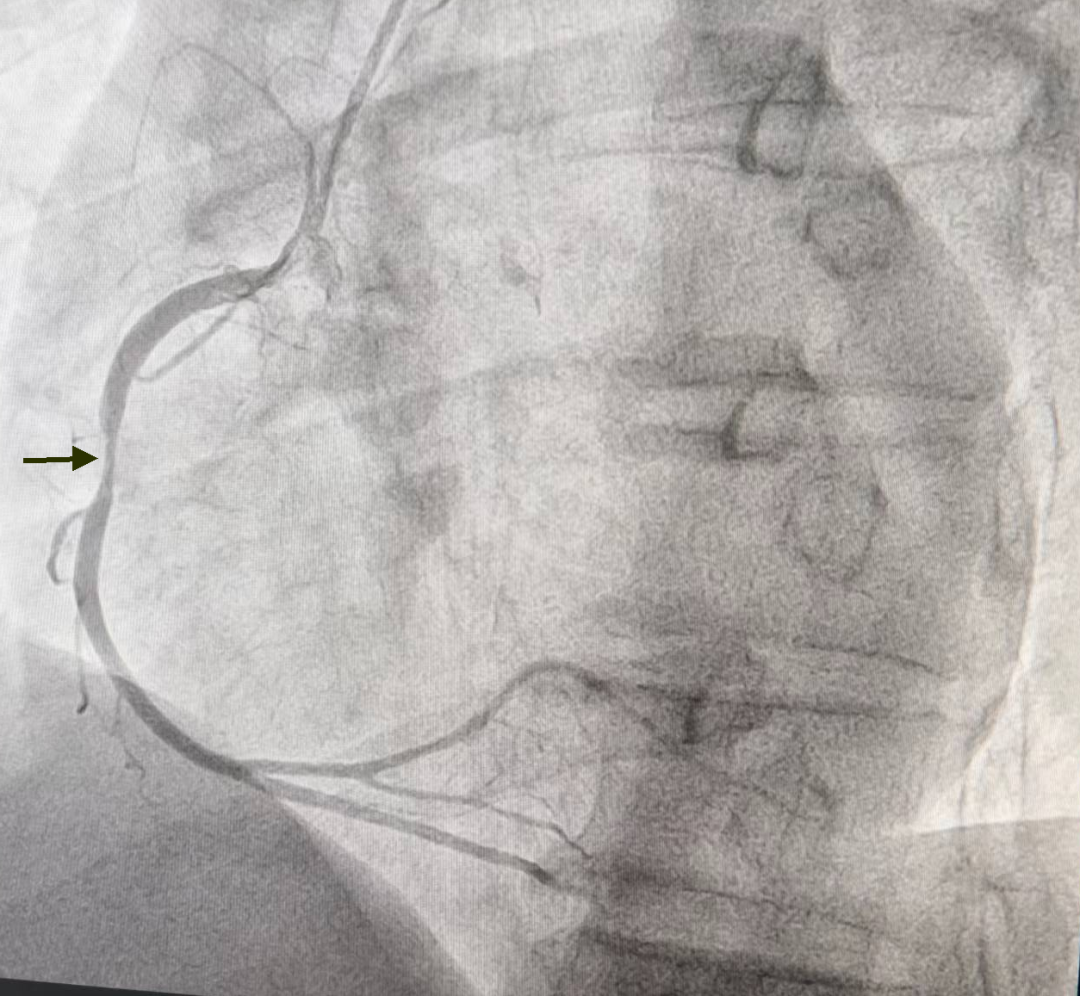

张院长看过病人后,迅速做出判断,并给出诊治方案:患者均为中老年男性,此次急性发病,均明确诊断为急性ST段抬高型心肌梗死,根据最新《急性ST段抬高心肌梗死诊断与治疗指南》,需尽早开通梗死相关血管,恢复心肌再灌注,两位患者发病均在6小时内,可选择静脉溶栓与急诊PCI术。与患者家属积极沟通,分别首先给予静脉溶栓治疗,均判定溶栓再通,溶栓后行冠脉造影提示病例1患者前降支近中段残余狭窄约70%,无需干预,规范药物治疗;病例2患者右冠脉“罪犯”血管残余狭窄80-90%,于右冠脉植入支架1枚,术后患者症状缓解,生命体征平稳,安全返回心内科重症监护室。